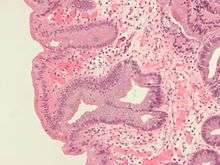

Intestinal metaplasia

The presence of goblet cells, called intestinal metaplasia, is necessary to make a diagnosis of Barrett's esophagus. This frequently occurs in the presence of other metaplastic columnar cells, but only the presence of goblet cells is diagnostic. The metaplasia is grossly visible through a gastroscope, but biopsy specimens must be examined under a microscope to determine whether cells are gastric or colonic in nature. Colonic metaplasia is usually identified by finding goblet cells in the epithelium and is necessary for the true diagnosis.

Many histologic mimics of Barrett's esophagus are known (i.e. goblet cells occurring in the transitional epithelium of normal esophageal submucosal gland ducts, "pseudogoblet cells" in which abundant foveolar (gastric) type mucin simulates the acid mucin true goblet cells). Assessment of relationship to submucosal glands and transitional-type epithelium with examination of multiple levels through the tissue may allow the pathologist to reliably distinguish between goblet cells of submucosal gland ducts and true Barrett's esophagus (specialized columnar metaplasia). Use of the histochemical stain Alcian blue pH 2.5 is also frequently used to distinguish true intestinal-type mucins from their histologic mimics. Recently, immunohistochemical analysis with antibodies to CDX-2 (specific for mid and hindgut intestinal derivation) has also been used to identify true intestinal-type metaplastic cells. The protein AGR2 is elevated in Barrett's esophagus,[11] and can be used as a biomarker for distinguishing Barrett epithelium from normal esophageal epithelium.[12]